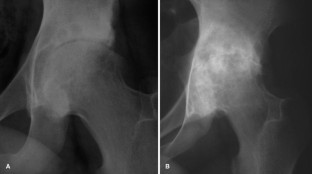

Fig. 3.